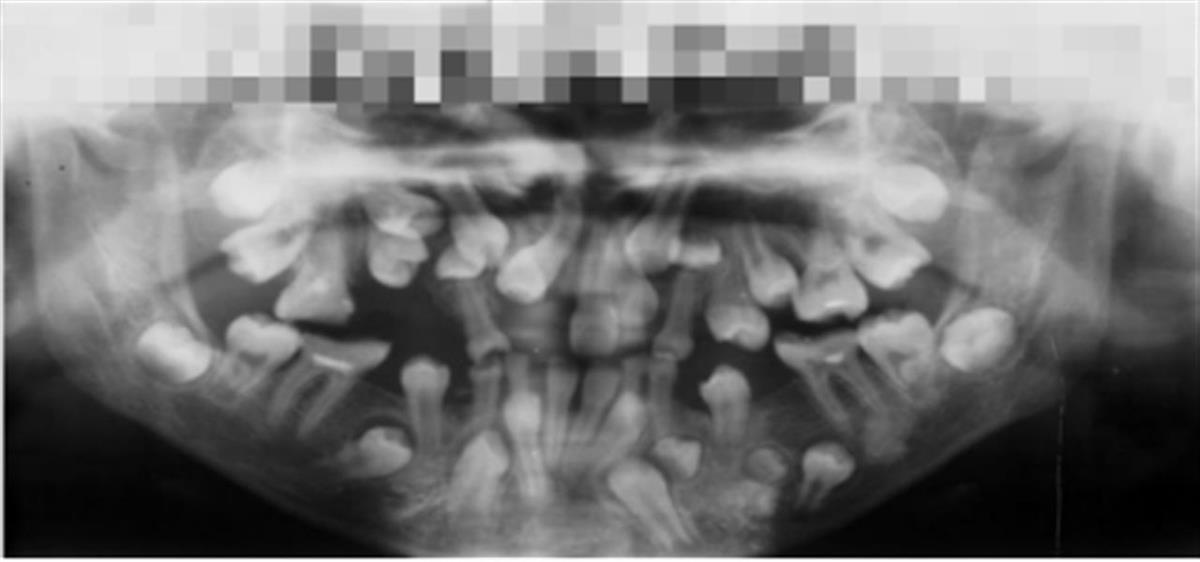

在障碍寰球多家病院无果后,小贝一家来到武汉大学东说念主民病院口腔科就诊,把柄口腔全景片,她的乳齿淹留、埋伏恒牙及多生牙数目均额外加多。

15岁的她本应总共替换的乳齿仍有十余颗未零散,而埋伏的恒牙如同“地雷阵”般深藏牙槽骨中。更难办的是,多生牙的挤压导致畴前牙齿错位,致使齐备无法萌出。经过详细评估,彭友俭教师建议她采取“双挨次渐进法”疗养。

15岁小贝的口腔全景片

15岁小贝的口腔全景片